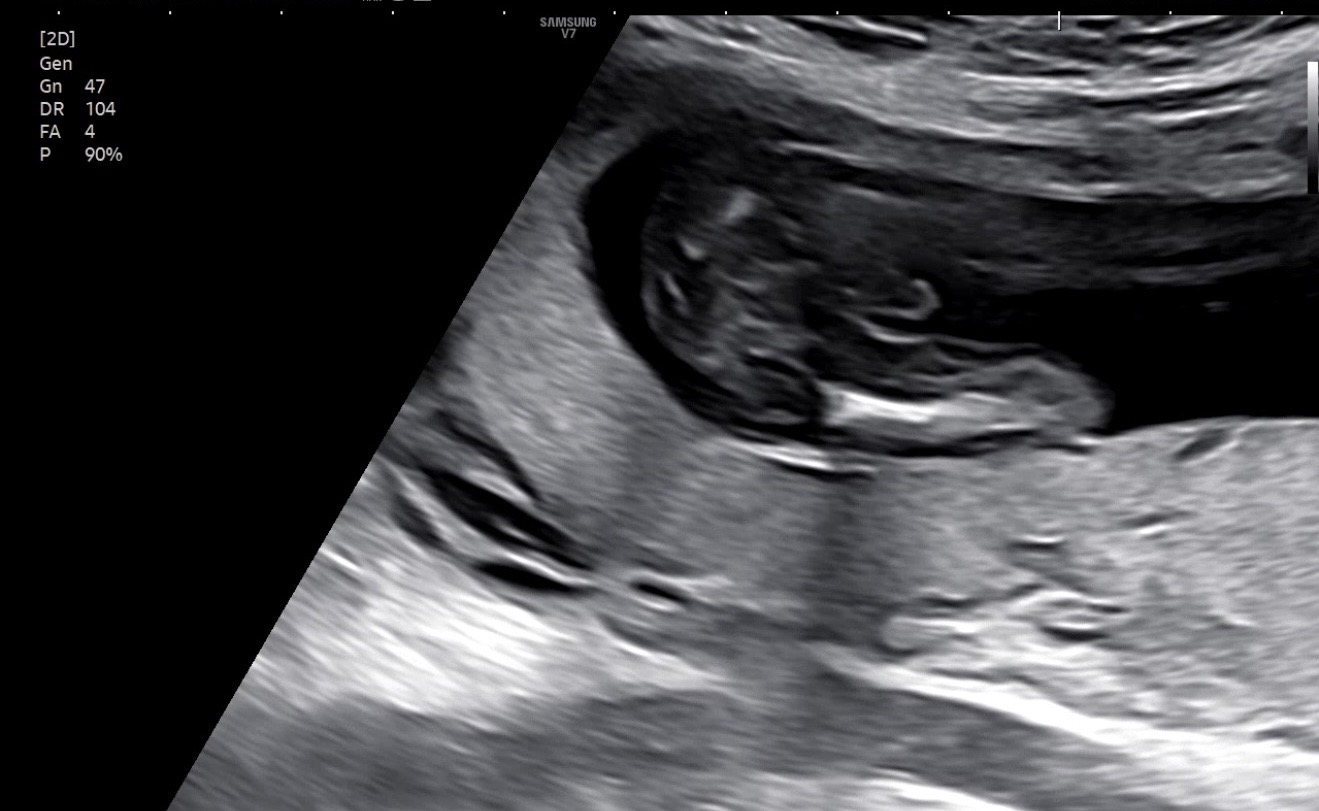

16주 성별 초음파 보고왔어요!

왕자라고 하셨는데 반전없을까요..? 뭔들~~건강만해라 생각했는데 첫째가 아들이라 둘째는 은근 딸을 바랬나봐요 ㅠㅠㅋㅋ 왕자인거 알구 조금 서운했다는..